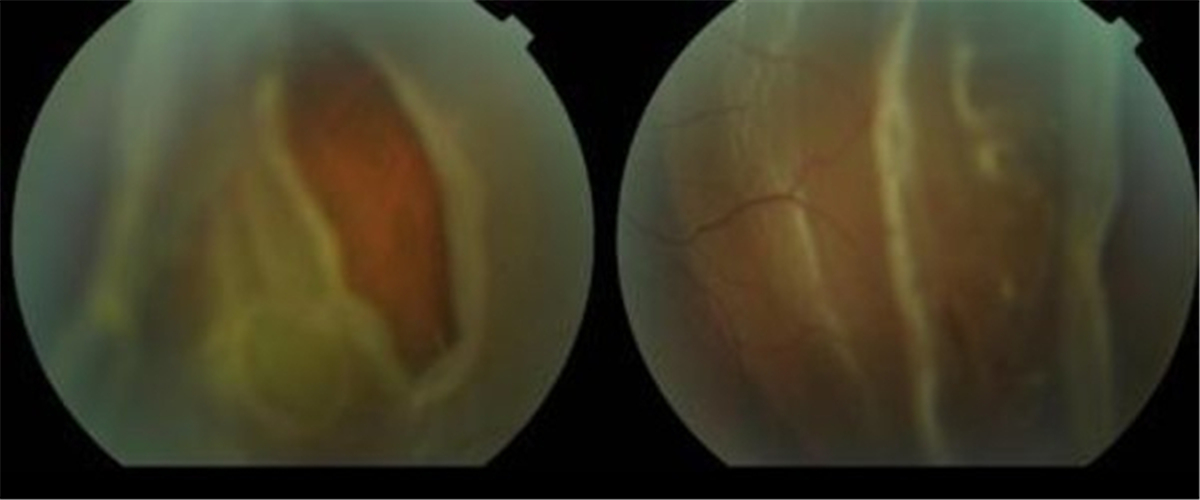

早產兒視網膜脫落

早產兒牽拉性視網膜脫落